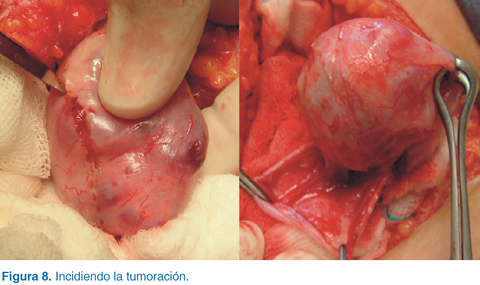

Se realizó laparotomía exploradora con abordaje a través de incisión en la línea media, se encontró tumoración en ovario izquierdo (Figura 7) y se hizo una incisión en la tumoración (Figura 8) hasta realizar salvamento de tejido ovárico (Figura 9) y visión final (Figura 10). El reporte histopatológico fue de teratoma maduro de ovario, con bordes libres de neoplasia. La evolución postoperatoria fue satisfactoria.